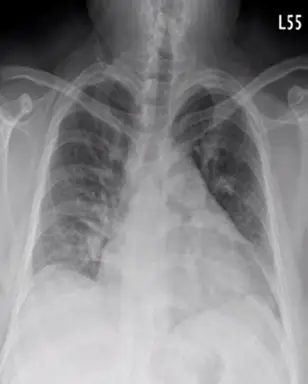

電腦斷層 (Image 3 - CT Coronal View):

- 表現:這是一張顯影劑增強的冠狀切面 CT。在充滿顯影劑(白色)的肺動脈主幹及其分支中,可見明顯的低密度充盈缺損 (Hypodense Filling Defect),佔據了血管腔的大部分。

- 意義:這是肺栓塞的確診影像 (Pathognomonic sign)。影像顯示血栓阻塞了肺動脈血流(可能為馬鞍型栓塞 Saddle embolus 或延伸至兩側主肺動脈),導致右心後負荷急劇增加。